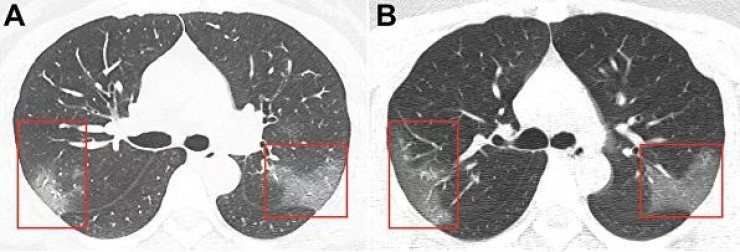

На первом снимке видны помутнения, создающие "эффект матового стекла". На втором, сделанном три дня спустя, можно заметить, что пораженная область расширяется.

"На основании эпидемиологических характеристик, клинических проявлений, изображений грудной клетки и лабораторных данных был поставлен диагноз: "пневмония 2019-nСоV", - говорится в публикации.